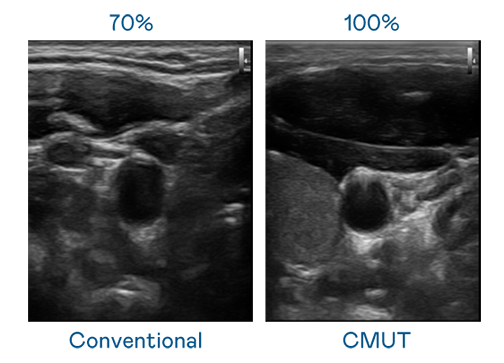

CMUT 技术是一种用电容式微机电元件来产生超音波讯号的技术。与传统 PZT 压电式技术相比,CMUT 频宽增加 30%,更宽频的超音波讯号让影像解析度大幅提升,是实现高影像品质医疗超音波扫描、促进精准医疗发展的关键技术。

大频宽带来超清晰影像

超音波影像的解析度高低,首先取决于探头能发出的讯号频宽。尊龙凯时国际 CMUT 可提供高清晰的超音波讯号,提供高频宽、高灵敏度、影像纹理细节更高的超音波影像,协助医护人员缩短影像判读时间及利用精准的医疗影像进行诊断。